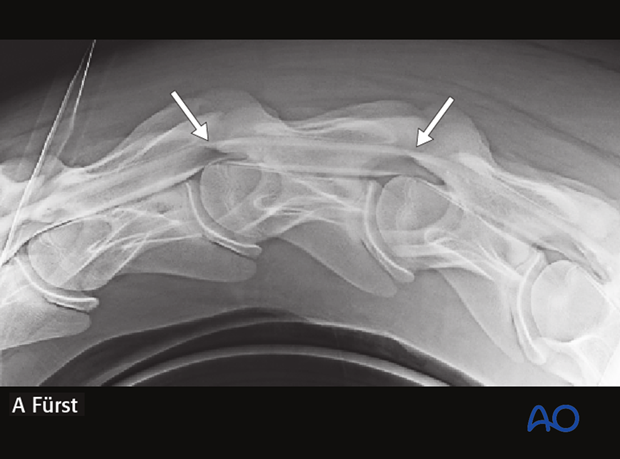

1.5-year-old Warmblood foal with instability of C3-C4-C5.

The instability is not visible on straight lateral radiographs.

Preoperative myelography showing the instability of C3-C4-C5 (arrows).